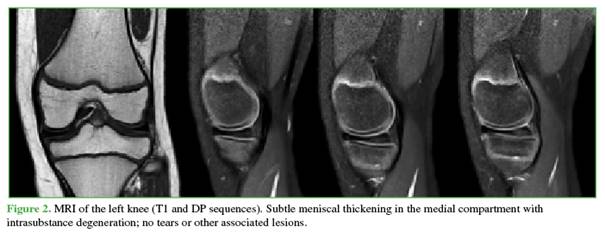

A 14-year-old male, with asthma and active in sports, presented to the Emergency Department with a two-week history of left knee pain sustained during soccer training. He had persistent pain associated with limping and intermittent locking. After initial evaluation and radiographs (Figure 1), outpatient management was chosen under the suspicion of a sprain. Symptoms decreased slightly, and locking ceased.